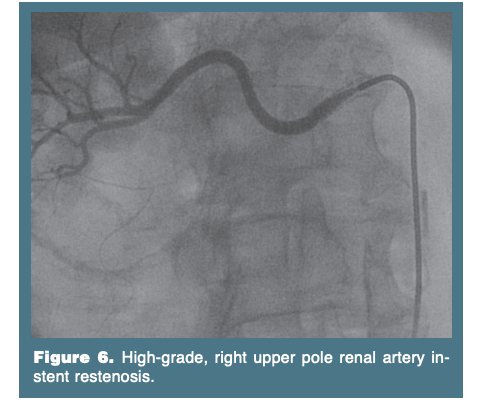

Restenosis with RAS is approximately 40% for arteries less than 4 mm in diameter, 14–18% for arteries 5.5 mm, and less than 10% for arteries greater than 6 mm in diameter.27 The overall restenosis rate for RAS is 17% (Figure 6).13,14 Restenosis following angioplasty of FMD lesions is usually less than 10%. Restenotic FMD lesions respond well to repeat balloon angioplasty. The mainstay for treatment of in-stent restenosis has been balloon angioplasty. The use of endovascular brachytherapy as an adjunct to angioplasty has also been reported.28 Although there are no data supporting the use for RAS, peripheral-size Cutting Balloons (Boston Scientific Corp.) provide an alternative to routine angioplasty for the treatment of in-stent restenosis. This requires the use of an 8-Fr guide, which poses a concern. It is occasionally necessary to place a second stent for a suboptimal angioplasty result.